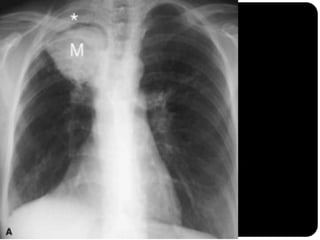

Massas

 São lesões com as mesmas características atribuídas aos

nódulos, porém com mais de 3cm de diâmetro.

Grande massa no lobo superior direito